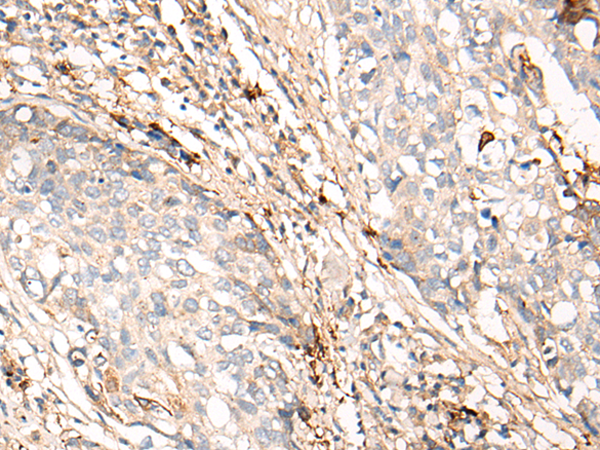

IHC positive control: |

Human lung cancer and human ovarian cancer |

IHC Recommend dilution: |

10-50 |